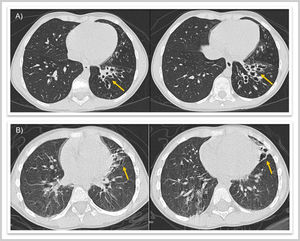

Caso 1. Varón de 8 años, sin antecedentes de interés, que presenta tos productiva de un año de evolución con atelectasia crónica del lóbulo inferior izquierdo (LII) en radiografías (RX) de tórax y bronquiectasias con engrosamiento mural y contenido mucoso en tomografía computarizada (TC) pulmonar (fig. 1). Se realiza broncoscopia flexible visualizando cuerpo extraño (CE) intrabronquial en LII que se extrae en el mismo procedimiento (fig. 2, vídeo), resultando ser una cáscara de pipa.

A.1) Caso 1. Radiografía de tórax con atelectasia de lóbulo inferior izquierdo (flecha roja). A.2) Caso 1. Tomografía computarizada con bronquiectasias en lóbulo inferior izquierdo (flecha roja). B.1) Caso 2. Radiografía de tórax con infiltrado paracardíaco izquierdo (flecha roja). B.2) Caso 2. Tomografía computarizada con atelectasia de língula y bronquiectasias (flecha roja).

Caso 2. Varón de 2 años, previamente sano, con súbita hemoptisis mientras saltaba en una cama elástica. En RX de tórax presenta infiltrado paracardíaco izquierdo y en TC pulmonar lesión «mal definida» en bronquio principal izquierdo con atelectasia de língula y bronquiectasias (fig. 1). En broncoscopia flexible se visualiza CE con importante edema e inflamación de mucosa adyacente, imposibilitando su extracción (fig. 2). Tras corticoterapia y antibioterapia intravenosa, se extrae mediante broncoscopia rígida, hallando una rama vegetal.

En ninguno se sospechó aspiración de CE por ausencia de episodio asfíctico, produciendo el retraso diagnóstico y la aparición de bronquiectasias, aún presentes 5 años después (fig. 3).